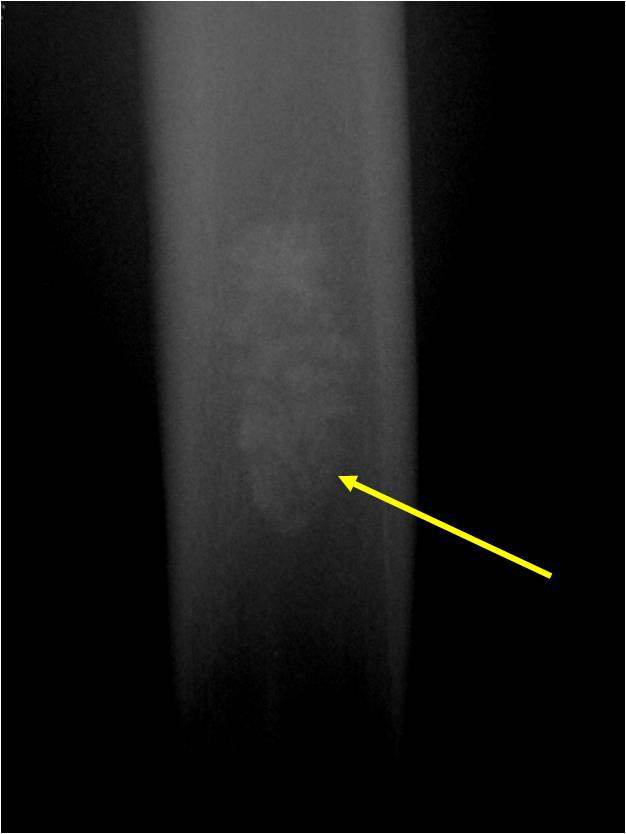

Radiographic Presentation

- Localized, radiolucent defect usually with punctate calcifications

- Calcifications are typical but not always present

- Matrix may demonstrate various degrees of calcification

- Calcifications are stippled, punctate, popcorn like calcifications and “Ring and Arc” calcifications

- Cartilage tumors grow in a lobular manner. The perimeters of the lobules undergo

- enchondral ossification that may calcify. If the entire perimeter of the lobule calcifies it appears

- radiographically as a “Ring”. If a portion of the perimeter of a lobule calcifies it forms an “Arc” on

- an X-ray.

Plain X-Ray:

- Geographic lytic lesion

- Central often metaphyseal in long bones

- Can be eccentric also

- Expansile remodeling with thinned cortex

- Chondroid matrix with calcifications in majority of tumors

- Approximately 20% have limited or no calcifications